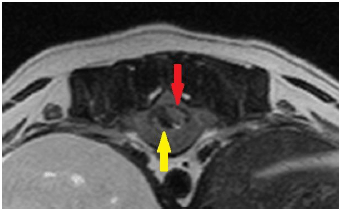

左は左前足と左後足が麻痺して歩けなくなったチワワの首のMRI画像、右が正常な子の画像です。

矢印の部分が脊髄ですが、左の画像はより白く映り、炎症が起こっているのが分かりました。 現在は治療によって症状は落ち着いています。

上は左前足と左後足が麻痺して歩けなくなったチワワの首のMRI画像、下が正常な子の画像です。

矢印の部分が脊髄ですが、左の画像はより白く映り、炎症が起こっているのが分かりました。 現在は治療によって症状は落ち着いています。 |